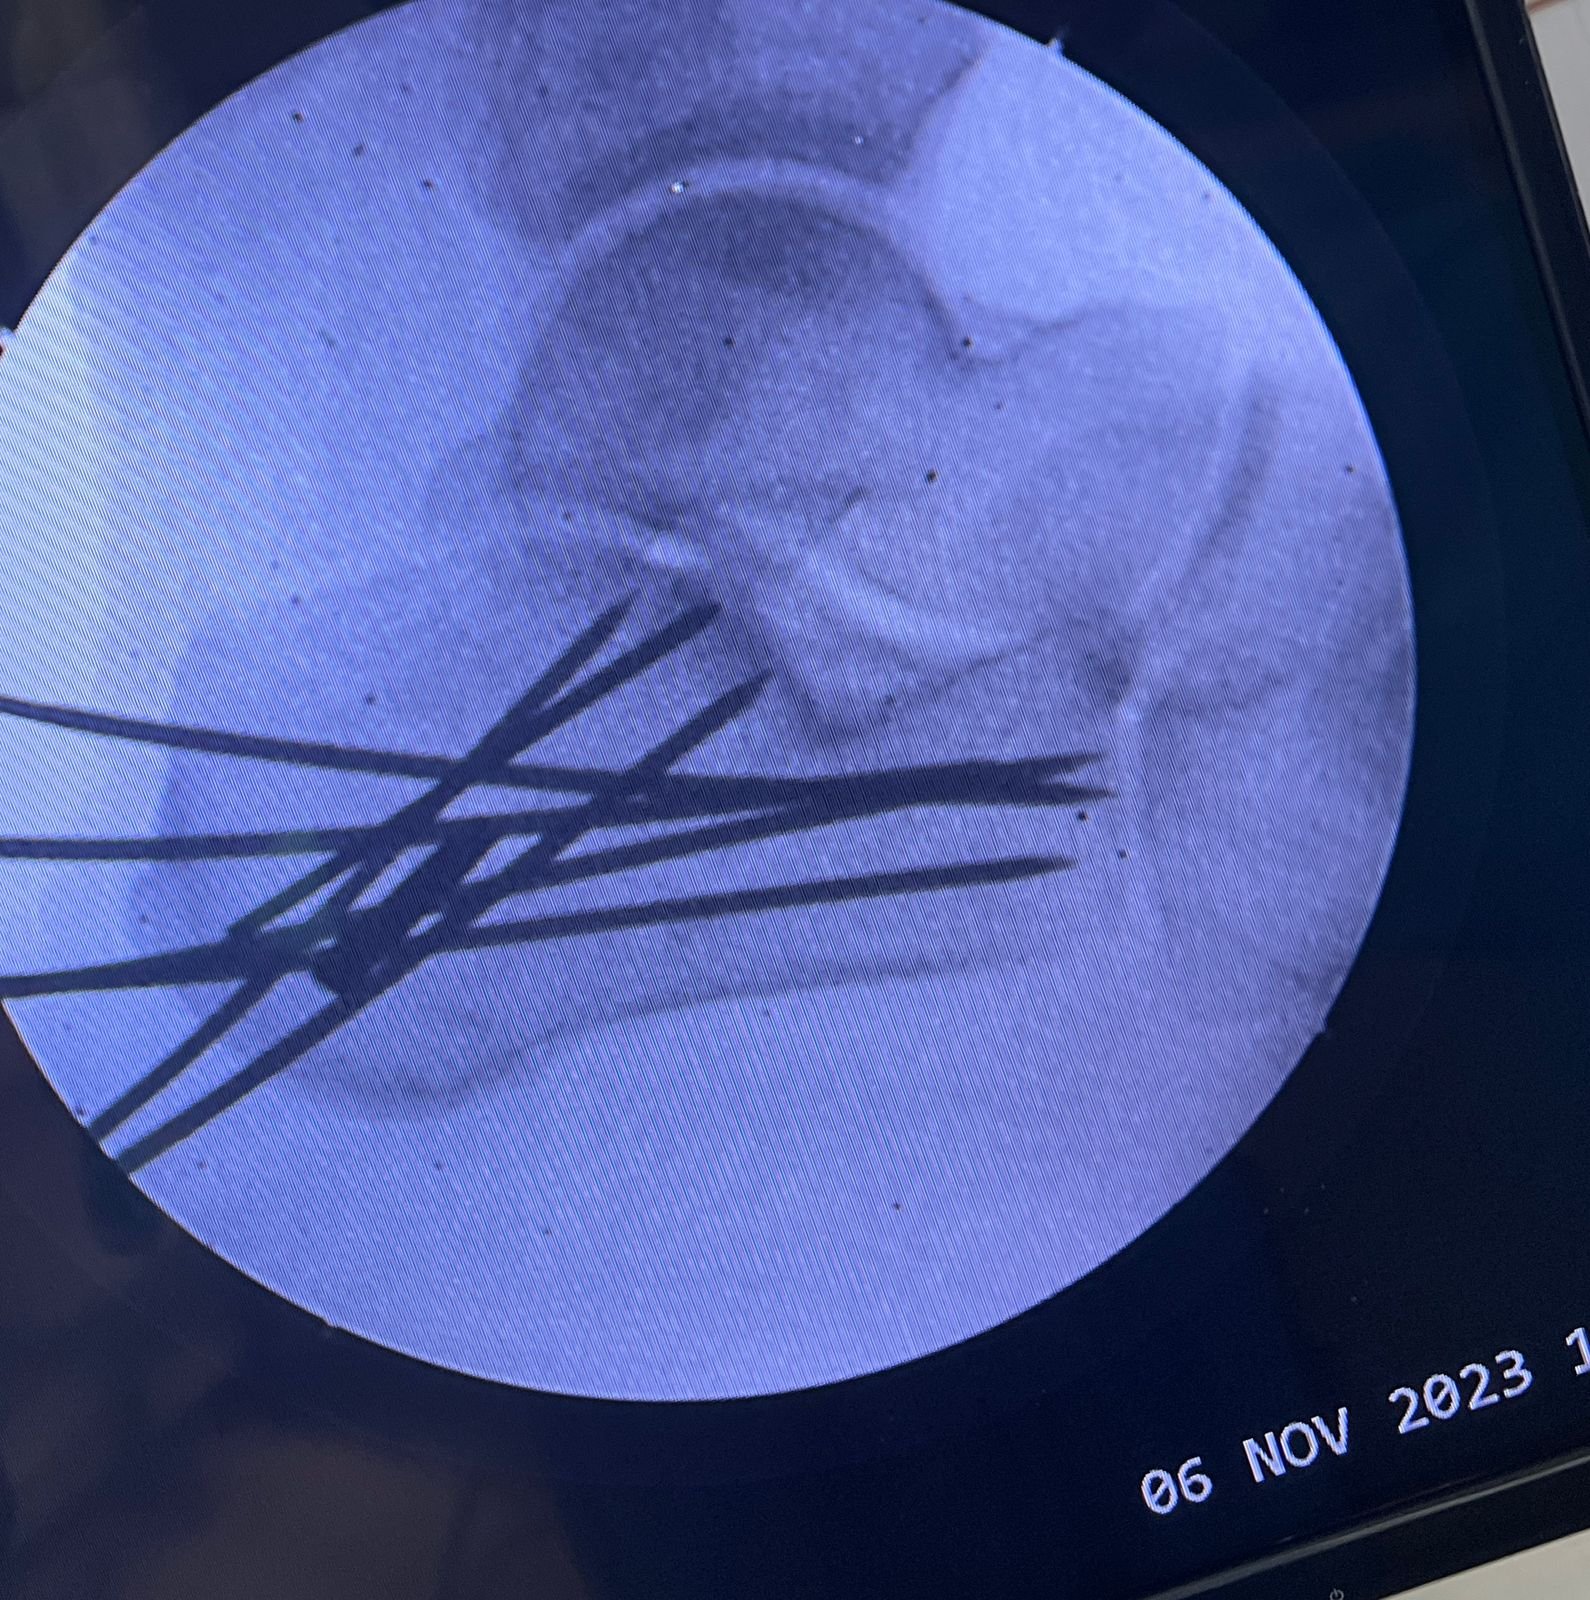

Clinic Exterior & Reception | Elbow dislocation &

operative treatment